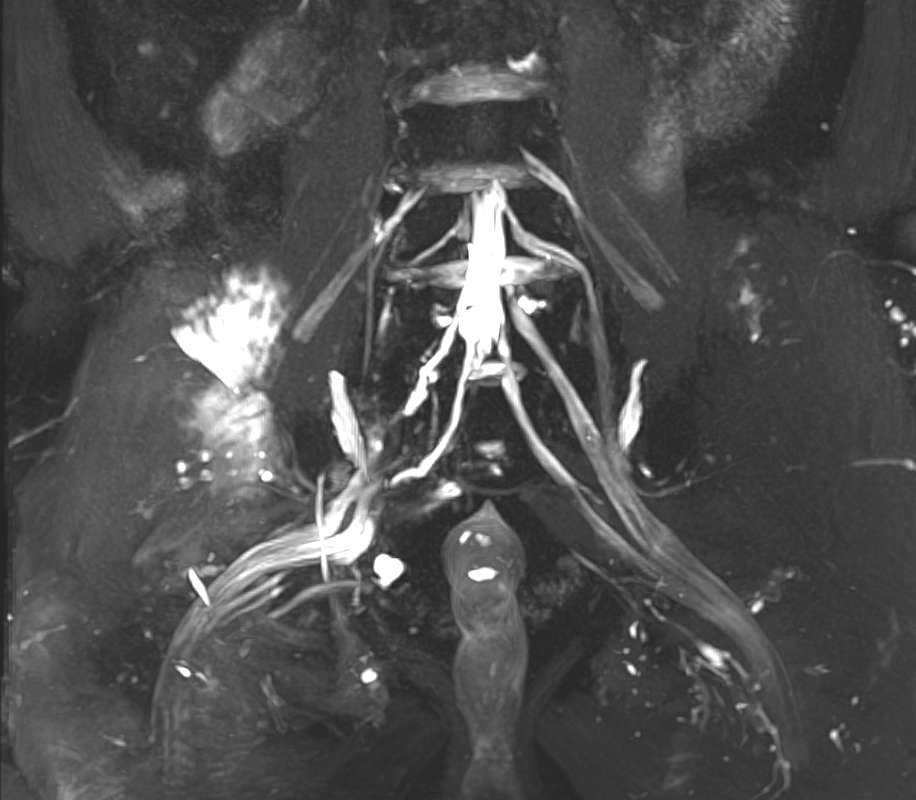

一位半年前不幸因车祸致多发创伤的老年患者,在外院已行四肢骨折内固定术,骨盆骨折是左侧侧方挤压型(LC-I型)行保守治疗,但伤后无骨折的右下肢一直无力,骨折顺利愈合后也毫无恢复,辗转多家知名医院,最终慕名来到北京积水潭医院。在门诊,经手外科、神经电生理科李文军主任医师仔细查体、阅片后,诊断为腰骶丛神经损伤、积水潭王氏分型的第III型:骶丛完全损伤(L4-S3)型,具体表现为高位的坐骨神经损伤(连枷踝+腘绳肌麻痹)伴臀肌麻痹(臀大肌、臀中肌)及鞍区感觉障碍。入院后,经王树锋主任医师带领的周围神经损伤治疗中心团队仔细评估和医患沟通后,决定应用骨科机器人辅助进行坐骨大孔扩大截骨,并采用远端神经移位术对腰骶丛神经进行修复。

患者腰骶丛神经磁共振检查示L4-S3损伤